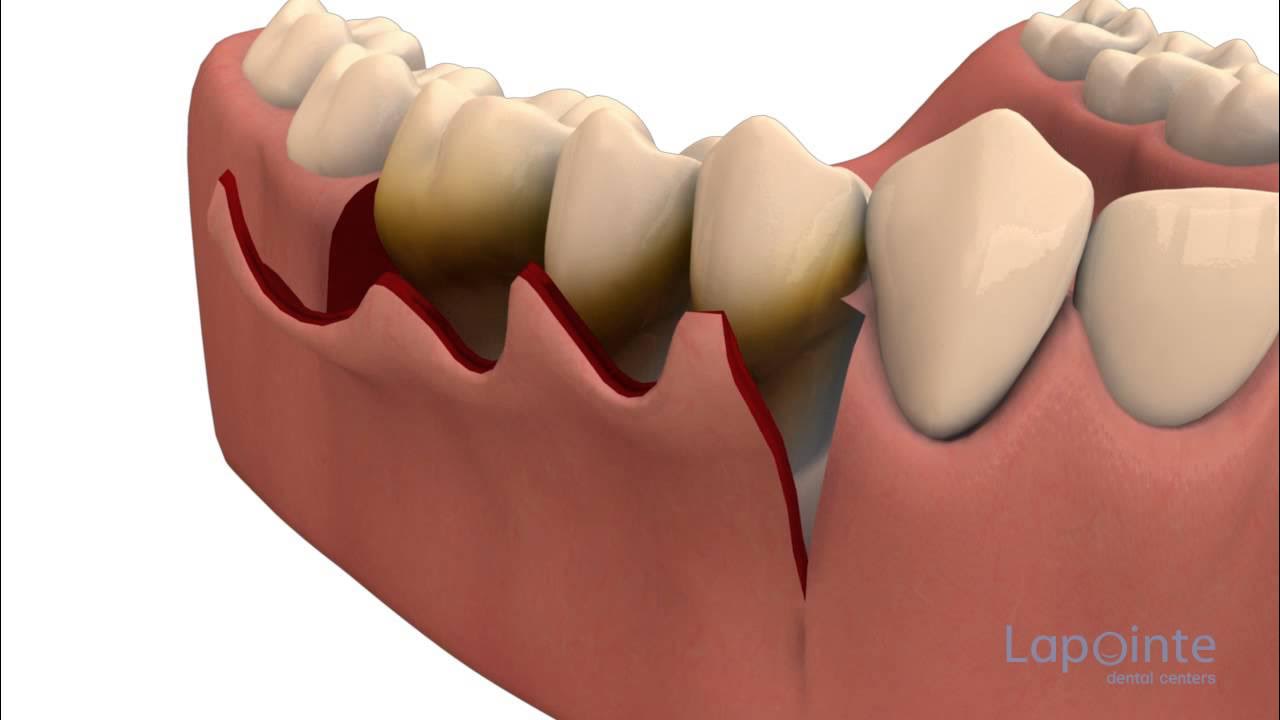

Is Laser Dentistry safe for gum treatment?

Yes. Laser dentistry is extremely safe and minimally invasive. At EndoElite, we use advanced dental lasers for gum surgery, depigmentation, and soft-tissue procedures with faster healing and minimal discomfort.